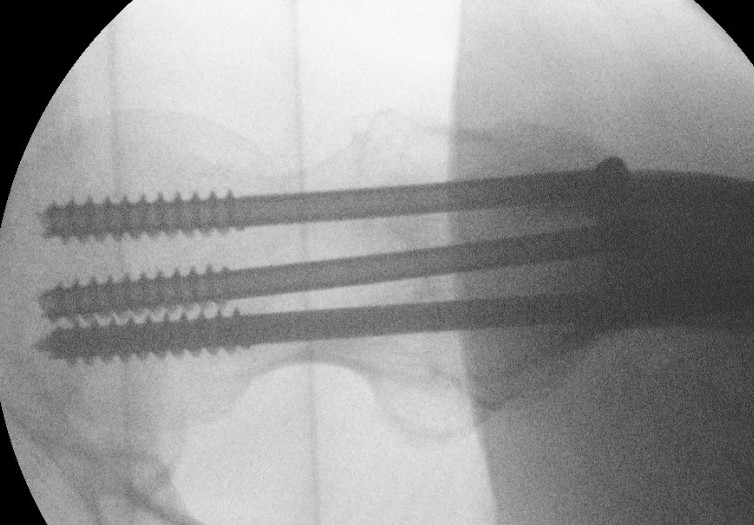

Cannulated screws

Technique

Lateral on traction table

- adequate reduction / no varus

- small incision or percutaneous

- 3 screws

- ensure inferior screw entry point is above lesser trochanter to prevent fracture

- ensure threads cross fracture site entirely to obtain compression

- need correct screw length so screw head can compress against cortex